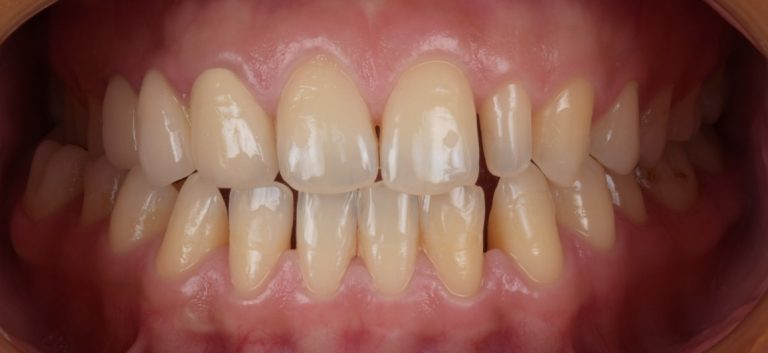

Classe I, morsure bord à bord, espacement, diastème

État initial

- Il s'agit d'un cas d'orthodontie combinée à une réparation esthétique.

- Il était nécessaire d'améliorer l'occlusion et la répartition de l'espace grâce à Invisalign et d'améliorer la forme et la beauté des dents du patient grâce à une restauration esthétique.

- Avant le traitement orthodontique, le patient a utilisé la conception esthétique DSD pour répartir l'espace, et l'espace dispersé en dehors de la zone esthétique a été ajusté par le mouvement proximal de la dent postérieure.

- Après traitement orthodontique, la partie supérieure droite 3, un implant posé et toutes les dents antérieures ayant reçu une restauration esthétique ont été utilisées.